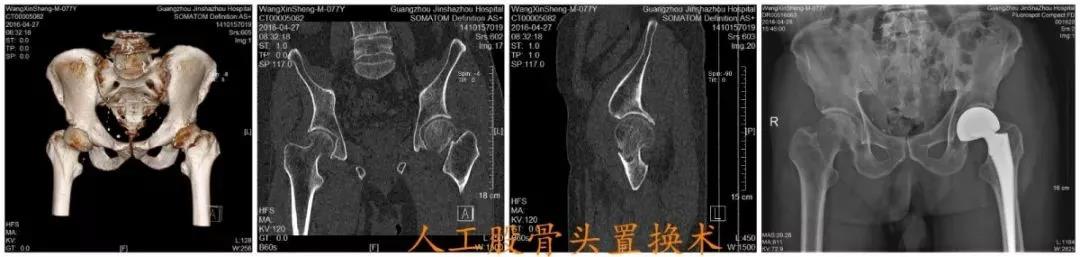

如果做了手术,比如关节置换,患者可以在短短几天后就下床,进行简单的活动,即使一些手术不能马上下床,但最起码可以在床上翻身、坐起。这些简单的动作可以有效的帮助患者把肺里的痰排出来,避免肺炎的发生,降低死亡率。